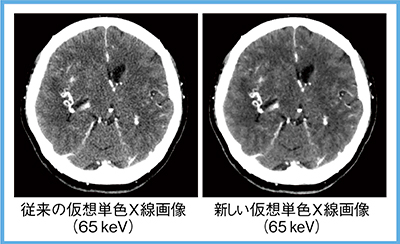

2.新しい仮想単色X線画像(W.I.P.)

仮想単色X線画像は,低エネルギーにするほどヨードのコントラストが向上するが,ノイズが急激に増加するという問題がある。東芝メディカルシステムズでは,この問題を解決するため,ノイズ増加を抑制する処理を組み込んだ新しい仮想単色X線画像を開発中である(W.I.P.)。

従来の仮想単色X線画像と新しい仮想単色X線画像(共にAIDR 3D FC13,65keV)を比較すると,新しい仮想単色X線画像ではノイズレベルが低下していることがわかる(図8)。FC13は線質硬化補正のない関数であるが,新しい仮想単色X線画像では頭部領域においても線質硬化現象によるアーチファクトがほぼない画像を得ることができる。この新手法では,病変検出能向上や造影剤の減量が期待でき,今後のリリースが待たれる。

図8 新しい仮想単色X線画像(W.I.P.)